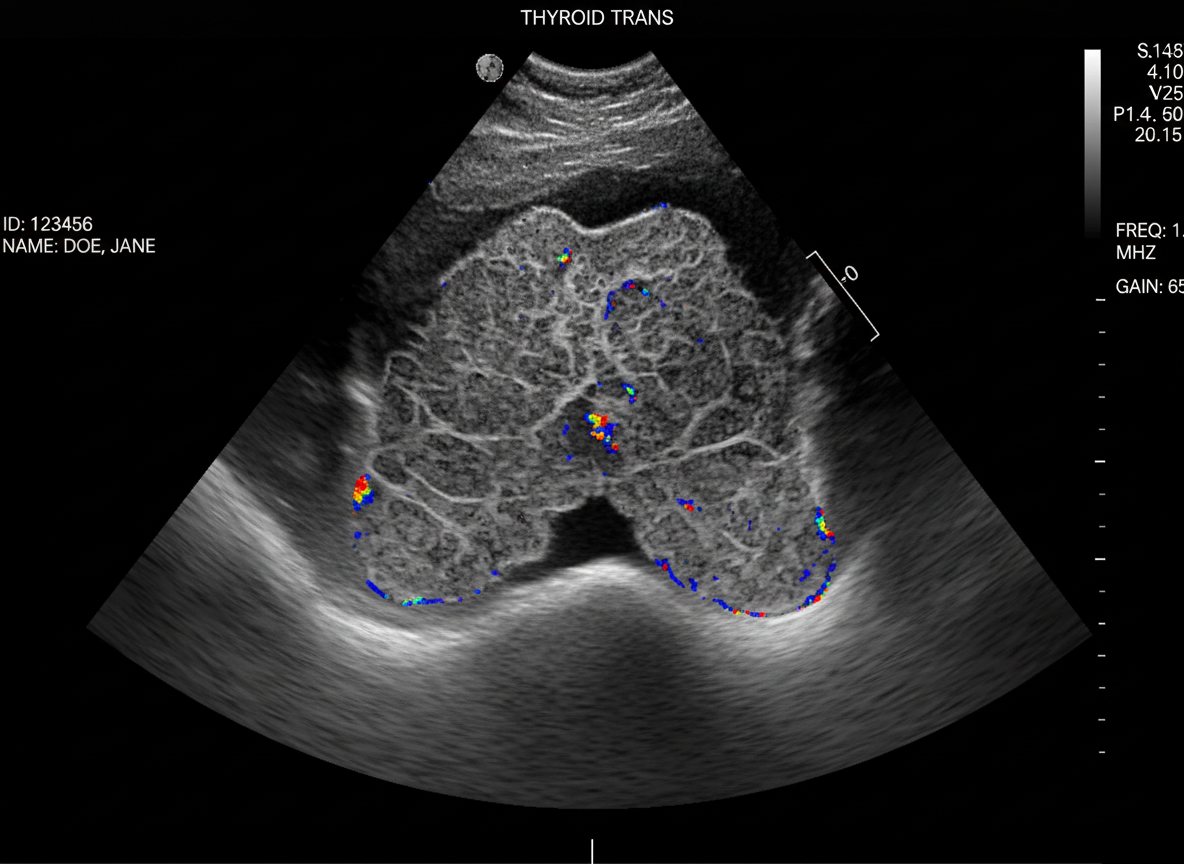

그 다음으로는 갑상선 초음파 검사를 하게 되는데,

이 초음파 검사를 통해

갑상선 결절의 유무와 크기, 모양 등을 확인할 수 있답니다.

초음파는 통증도 없고 아주 간단한 검사라서

부담 없이 받으실 수 있을 거예요.